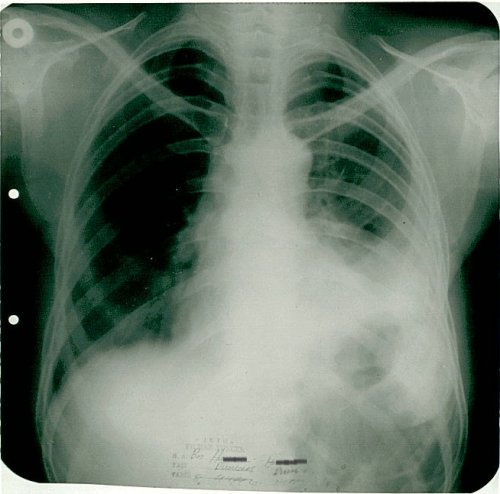

1995: 31 yaşındaki erkek hasta öksürük, ateş ve sırt ağrısı ile başvurdu.

Biyopsi sonucu "küçük hücreli anaplastik karsinom" teşhisi kondu.

Röntgende kitle küçülmüş durumda görüldü.

Röntgen tümörün tamamen kaybolduğunu gösterdi.

Radyolojik Kanıt: Röntgende tümör tamamen kayboldu